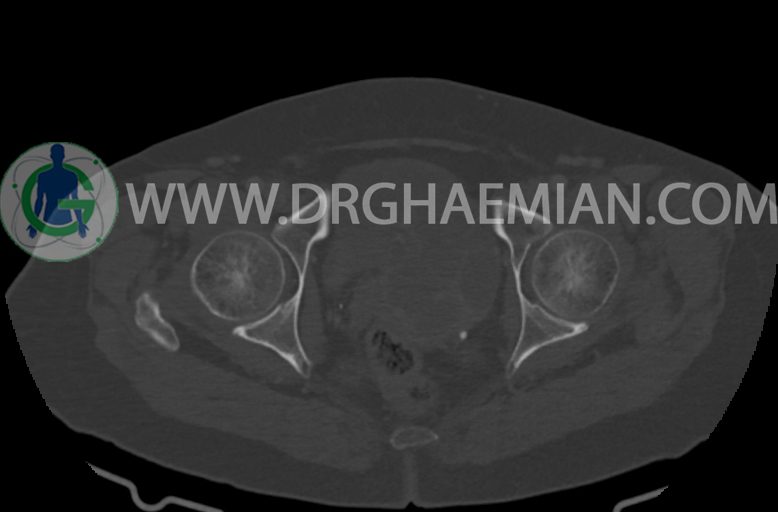

سی تی اسکن شکم و لگن با استفاده از اشعات ایکس تصاویر عرضی از ناحیه شکم و لگن ایجاد میکند. در این کیس موسینوس کیست آدنوما، شواهد هیسترکتومی، ضایعه در سمت راست لگن، کیست در کبد و … دیده می شود.

–ساختار Cystic multiseptate همراه با Enhancing thick septation به ابعاد 79x62mm در

لگن دیده می شود که در درجه اول مطرح کننده ی ضایعات نئوپلاستیک تخمدانی نظیر mucinous cyst adenocarcinoma است.

–ضایعه ی mass like هیپردنس- هتروژن به قطر 42mm در سمت راست لگن